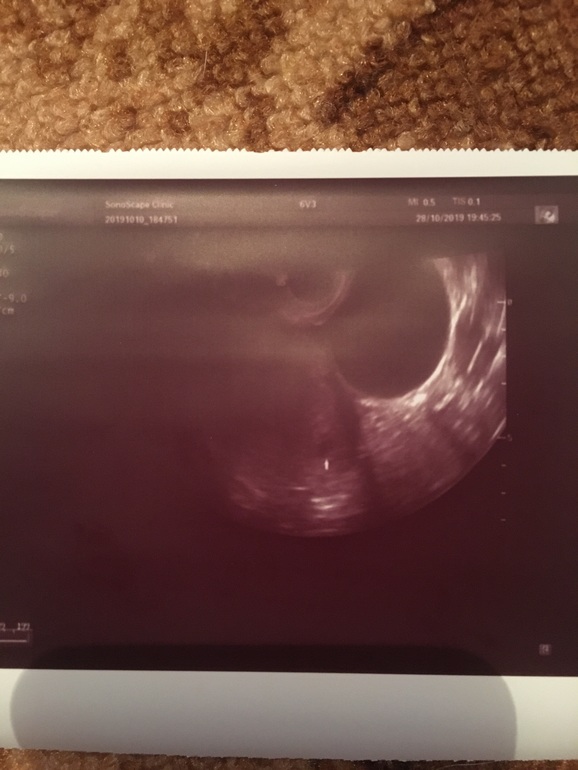

На узи сегодня была, нашли плодное яйцо в матке(слава богу🙏🏼), через 10 дней ещё раз прийти для контроля.

Овуляция приблизительно была 6.10. Врач сказала что ПЯ соответствует сроку беременности, но меня смущает что оно очень маленькое.

У кого так было, расскажите поподробнее) а то немного волнительно) я думала что на этом сроке был бы виден эмбрион😌